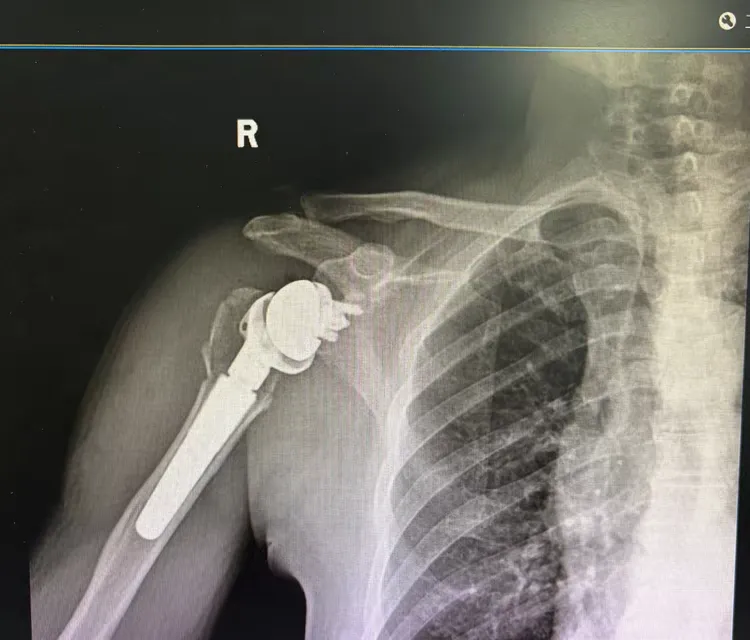

↑术后第二天患者右肩影像学资料

术后次日,邓先生肩部疼痛明显缓解,可在医护指导下开展肩关节被动活动,目前恢复状况良好,关节功能正逐步恢复。作为前沿骨科技术,反式肩关节置换术通过创新逆向设计重构肩关节旋转中心,弥补肩袖功能缺陷,能快速缓解疼痛、提升关节活动范围,助力患者恢复生活自理能力。